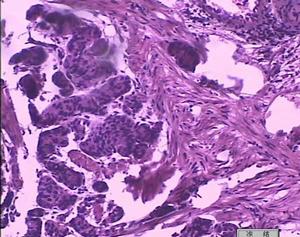

1.光學顯微鏡發生急性腎功能衰竭的本病患者,腎臟活檢光學顯微鏡下,通常發現一些腎小球內有廣泛的毛細血管增生或腎小球毛細血管損害伴新月體形成大量的內皮下沉積物以及大而圓的管腔內血栓。這些血栓為大的內皮下沉積物,或是冷球蛋白在管腔內的沉積,有時候在單核細胞內沉積。通過非特異性酯酶染色發現,這些損害在這些細胞內是很常見的。1/3的腎臟活檢標本可見明顯的血管炎。

2.免疫螢光顯微鏡可發現在毛細血管壁、腎小球膜的顆粒狀沉積物和管腔內的C3、IgG和。IgM團塊狀沉積物,這些沉積物在免疫學上與循環中的冷球蛋白相似。只有少量的C1q沉積,間質中可有IgM沉積。

3.電子顯微鏡可以發現在毛細血管壁的大塊沉積物和晶狀結構的電子密度沉積物。